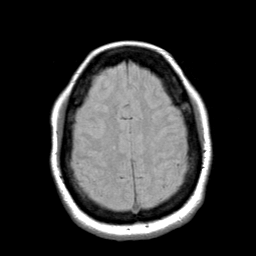

Cerebral hemorrhage, MR Study mr-pd -- Slice #18

[Home][Help][Clinical] Slice 18